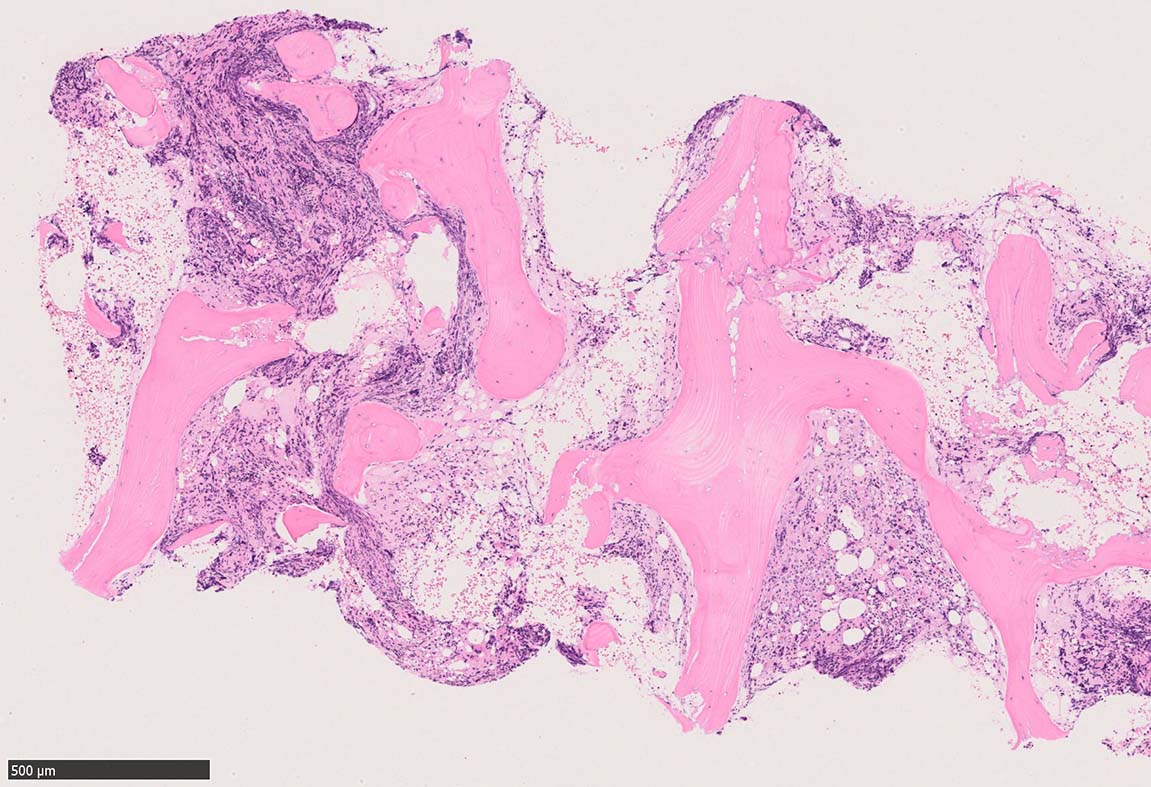

Case02; Meylofibrosis, overt fibrosis

77year-old female. 40歳時polycythemia veraと診断されていた.

[注] この症例は詳細は不明であるが, 過去にPVと診断されているため, PVに伴う二次性のmyelofibrosisの診断になる.

黒染する弾性線維の増生のほか, 赤く染まる膠原線維の増生が確認される. MF-2 fibrosis. 鍍銀染色の核染色をすると膠原線維の赤染がわからなくなるので行わない.